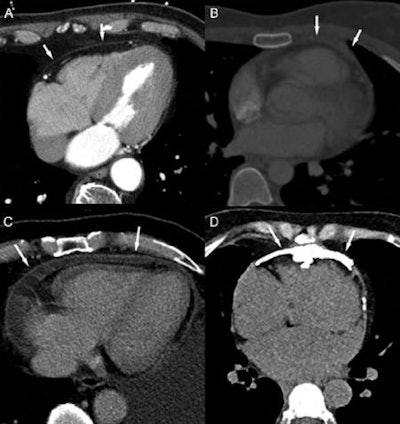

Cardiac CT

CT excels in the assessment of coronary arteries, its ability to evaluate coronary calcium without contrast, and high sensitivity and specificity for ruling out coronary artery disease. And obstructive CAD is likely rare without detectable calcium after irradiation.

CT is hampered by its limited ability to evaluate the severity of stenosis, although emerging applications to determine the hemodynamic significance of coronary stenosis, including stress myocardial perfusion CT and fractional flow-reserve CT computer-simulated fractional flow reserves based on CT could alter the picture. Late contrast enhancement at CT can also pick up myocardial scars.

In limited studies of patients after radiation therapy for Hodgkin's disease, CT found advanced coronary calcification and obstructive coronary disease in the young cohort; however, it is unclear if CT can distinguish general atherosclerotic disease from atherosclerosis caused by radiation therapy, the authors wrote. Absent symptoms of coronary disease, there is probably insufficient data to recommend the use of CT after radiation therapy, the authors wrote.